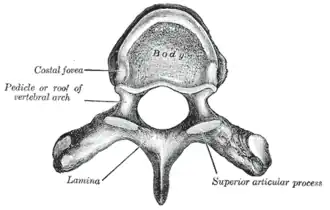

A typical thoracic vertebra, viewed from above.

A typical thoracic vertebra, viewed from above. -

The vertebral bodies in the middle of the thoracic region are heart-shaped and as broad in the anteroposterior as in the transverse direction. At the ends of the thoracic region they resemble respectively those of the cervical and lumbar vertebrae. They are slightly thicker behind than in front, flat above and below, convex from side to side in front, deeply concave behind, and slightly constricted laterally and in front. They present, on either side, two costal demi-facets, one above, near the root of the pedicle, the other below, in front of the inferior vertebral notch; these are covered with cartilage in the fresh state, and, when the vertebrae are articulated with one another, form, with the intervening intervertebral fibrocartilages, oval surfaces for the reception of the heads of the ribs.

The pedicles are directed backward and slightly upward, and the inferior vertebral notches are of large size, and deeper than in any other region of the vertebral column.

The laminae are broad, thick, and imbricated – that is to say, they overlap those of subjacent vertebrae like tiles on a roof and connect with the pedicles to surround and protect the spinal cord.

The intervertebral foramen is small, and circular, with two at each intervertebral level, one for the right and one for the left exiting nerve roots.

The vertebral foramen is the large opening posterior to the vertebral body also known as the spinal canal. It contains and protects the spinal cord at the thoracic level.

The spinous process is long, triangular on coronal section, directed obliquely downward, arising from the lamina and ending in a tuberculated extremity. These processes overlap from the fifth to the eighth, but are less oblique in direction above and below.

The superior articular processes are thin plates of bone projecting upward from the junctions of the pedicles and laminae; their articular facets are practically flat, and are directed backward and a little lateralward and upward.

The inferior articular processes are fused to a considerable extent with the laminae, and project slightly beyond their lower borders; their facets are directed proximally, medially, and inferiorly to the lamina.

The transverse processes arise from the arch behind the superior articular processes and pedicles; they are thick, strong, and of considerable length, directed obliquely backward and lateralward, and each ends in a clubbed extremity, on the front of which is a small, concave surface, for articulation with the tubercle of a rib.